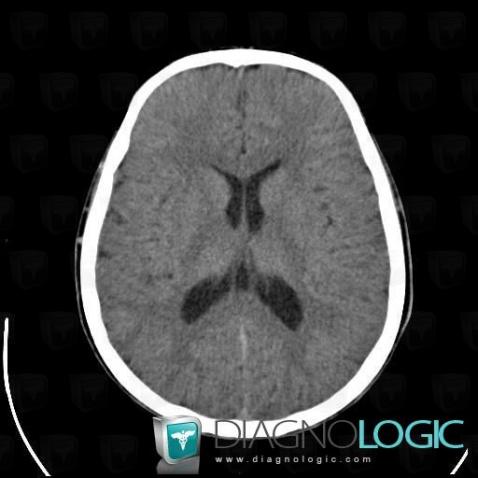

The images below illustrate this case for diagnoses Cavum veli interpositi, for the modalities (CT)

Cavum veli interpositi, Cerebral hemispheres, Cerebral falx / Midline, CT

- Diagnosis Cavum veli interpositi, Location(s) Cerebral hemispheres, with gamuts Hypodense intracerebral lesion on noncontrast CT, Intracerebral CSF intensity lesionCerebral falx / Midline, with gamuts Midline mass